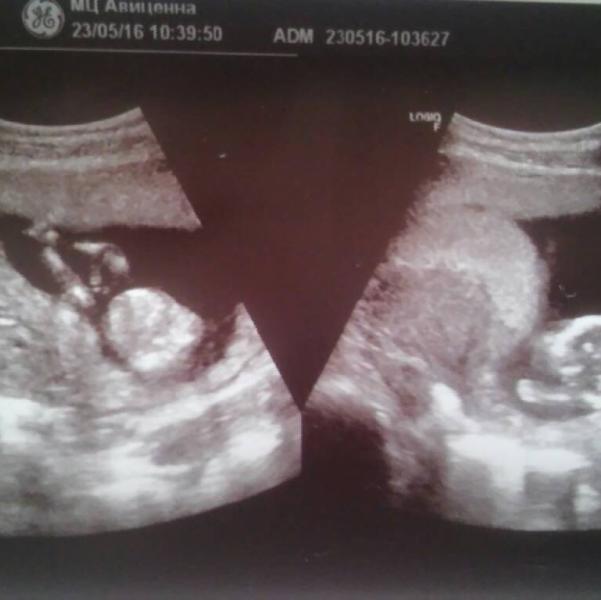

14 недель ровно, сходила на узи! У нас все хорошо, развиваемся по сроку, только есть небольшой тонус!

Врач очень уверенно сказала что будет второй сынок, говорит это очевидно! Но ведь на этом сроке большая вероятность ошибиться! Мы пришли вместе с мужем и сыном, и муж сразу увидел на экране причендальчики знакомые, как с первым сыном было на узи!)) Теперь муж вообще не сомневается, а я в раздумьях!) Кому на таком сроке точно сказали и потом подтвердилось?)